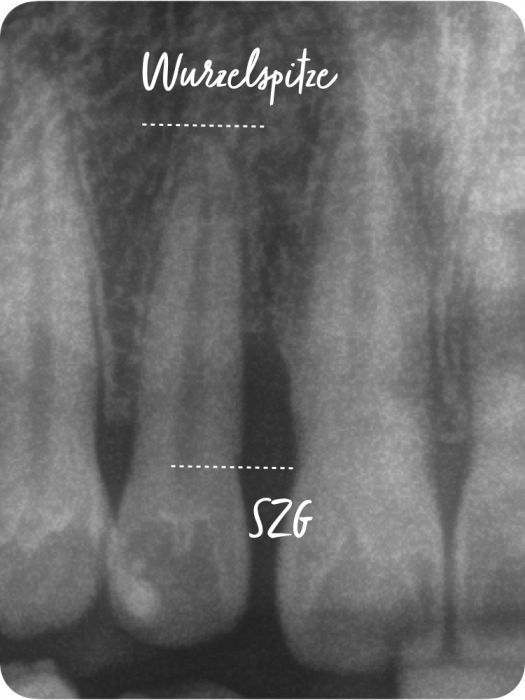

Der Grad enthält Informationen zur Progressionsrate der Erkrankung und dem Vorliegen von patientenspezifischen Risikofaktoren (Nikotinkonsum und Diabetes/HbA1c). Die Progressionsrate kann direkt anhand von Vorbefunden abgeschätzt werden oder indirekt durch den sogenannten Knochenabbauindex (KA %/Alter). Dabei wird der Zahn auf dem Röntgenbild berücksichtigt, der den stärksten marginalen Knochenabbau hat. Das Vorliegen von Risikofaktoren kann zu einem Upgrade führen. Fehlen diese Risikofaktoren, führt das aber nicht zu einem Downgrade.